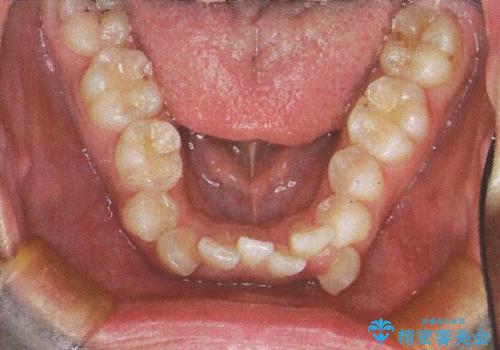

- 前歯のガタガタを主訴に来院されました。

前歯の重度のガタガタで、八重歯もある状態でした。

また右下の乳歯が残っており、永久歯が1本足りませんでした。